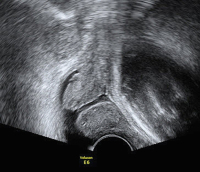

Abbildung

Ultraschall-Serometra

Abbildung 1: Serometra bei Asherman-Syndrom nach manueller Plazentalösung und dreimaliger Abrasio nach der letzten Entbindung. Dank der Flüssigkeit kann man erkennen, dass praktisch keine Endometrium-Schleimhaut aufgebaut ist.